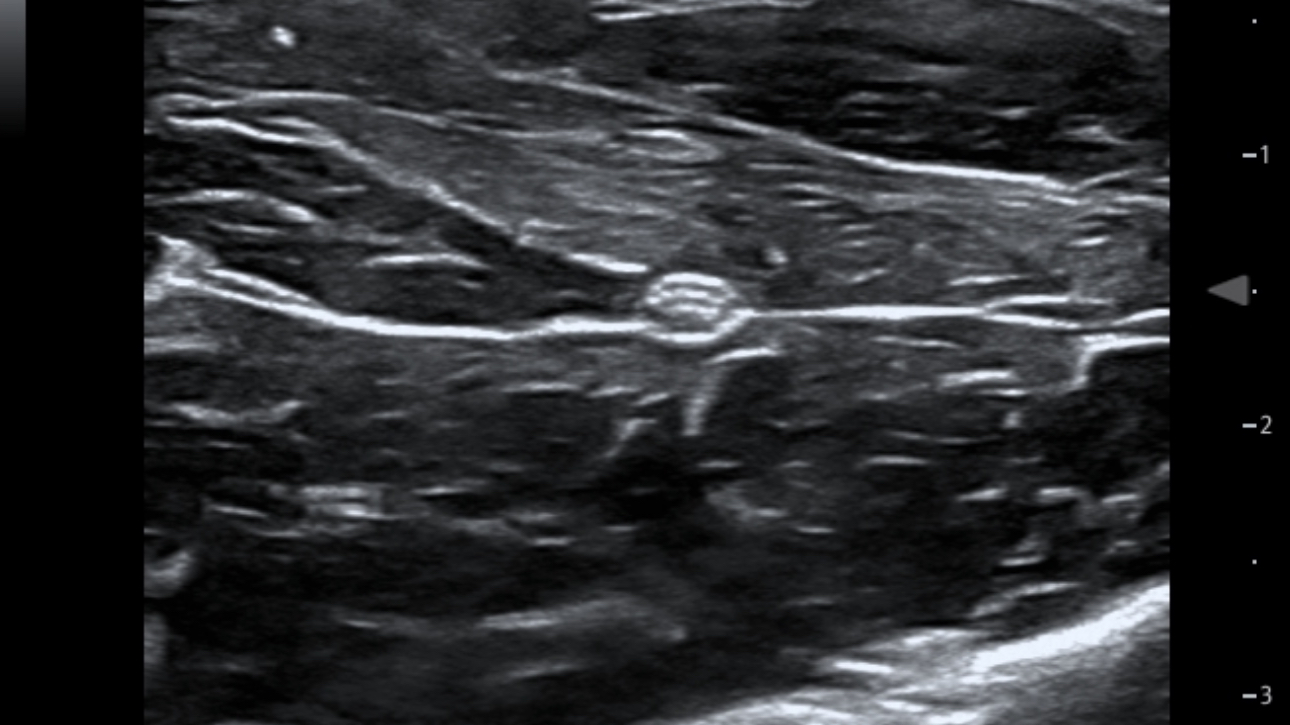

eSpacial Navi??and iNeedle+TM?ensure safe needling solution. Up to 20MHz ultra-high frequency linear transducer can visualize the finest nerves and fibers with extremely high resolution. Seamless monitor with full touch screen and exclusive clean-lock function ensure efficient cleaning and disinfection. The multiple modality design enables the TE5 to easily handle a wide range of medical scenarios.